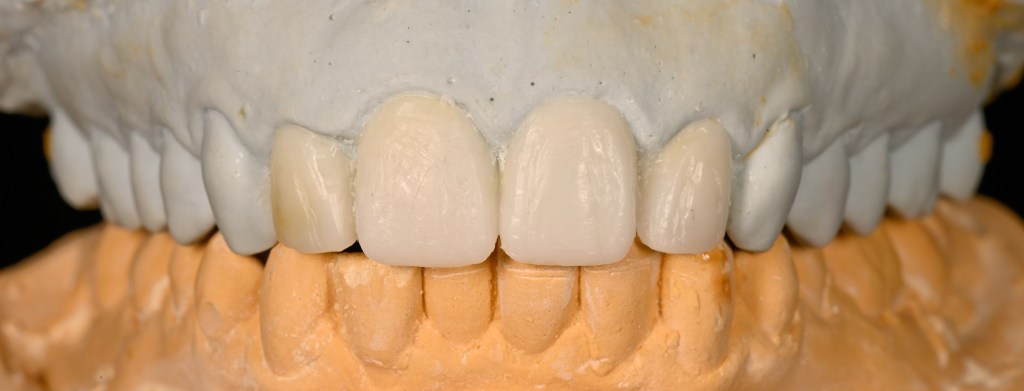

Completed four unit Emax Press Crown wax up #6-10